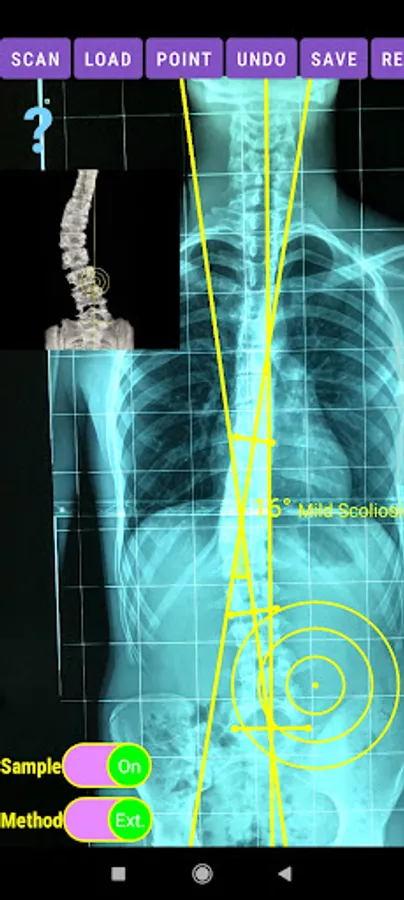

-Offers a very convenient way to determine the most accurate possibly way at once. By marking four points at the same X-ray, at each spine the App calculates the Cobb angle. In cases where values are out of normal ranges, the scoliosis is categorized according to measured angle as mild, moderate, severe. To simplify the process and to minimize inter-observer errors usually by not selecting the actual end vertebra, the app offers also in ext mode the ability to draw the vertical reference line through the patient’s sacrum and to identify more easily the end vertebrae (ext method).

The app offers a very convenient way to asses spinal deformity by measuring the Cobb angle. The first thing is to load one image from your photo library or capture a photo from x-rays photos of a patient. The app offers two measuring methods, the simple (Sim.) and the extended (Ext.). By clicking the relevant option, the option is highlighted and the respective method is activated.